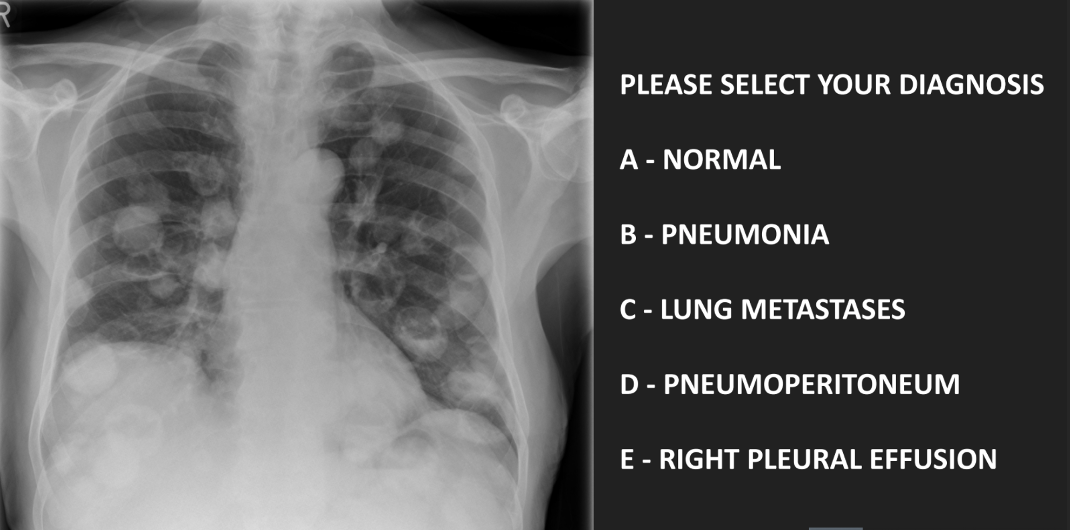

diagnose

A

C - lung metastases

• ‘Canon ball mets’

• Older patients

• Primary sites: bowel, renal cell, pancreatic and breast cancer